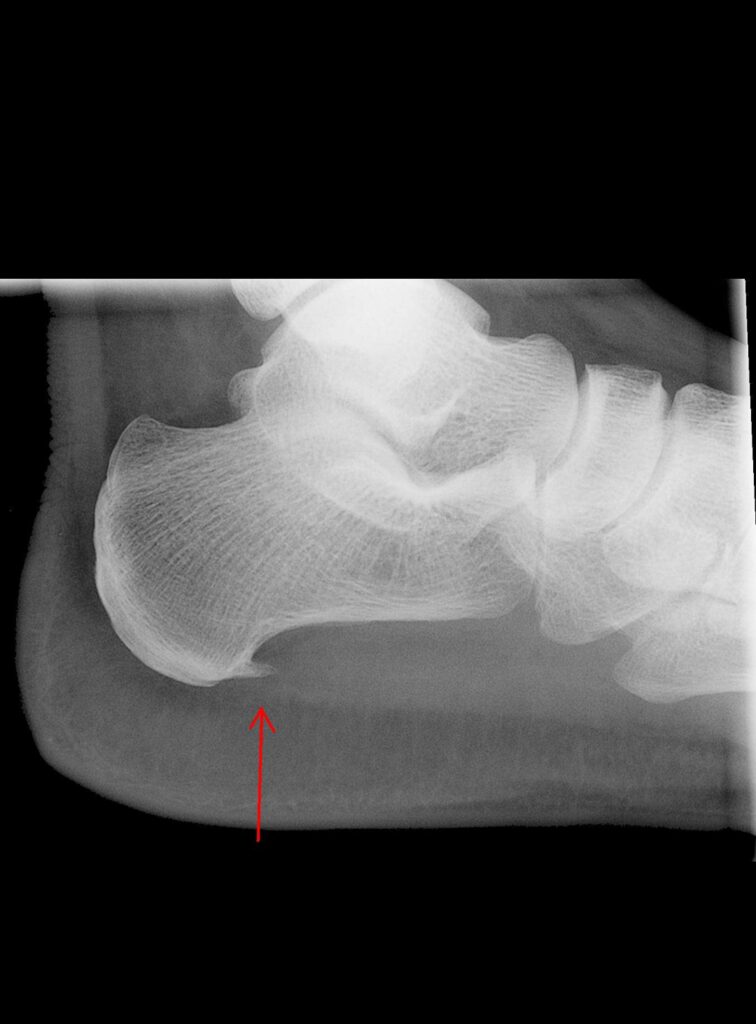

El espolón calcáneo es una excrecencia ósea que se forma en la parte inferior del hueso calcáneo. Suele estar asociado a una fascitis plantar crónica, siendo esta la verdadera responsable del dolor en la mayoría de los casos.

En una radiografía es frecuente observar el espolón, aunque no siempre es el tamaño del espolón lo que determina el dolor, sino la inflamación y degeneración de los tejidos que lo rodean.